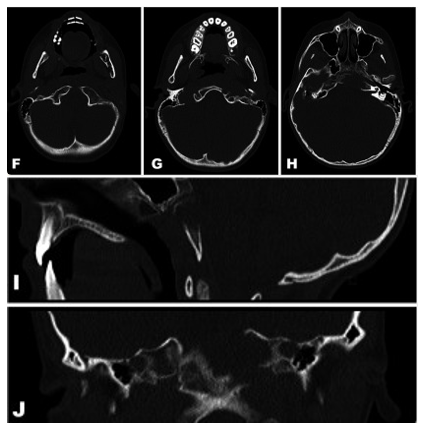

术前CT:左侧岩骨及斜坡骨质存在骨溶解性病灶。

"不符合脊索瘤的特征!"

这个病变反常地侵袭了咽旁肌,这与典型的脊索瘤特征不符。全身MRI排除了其他骨骼病灶的可能,而SPECT检查仅显示病变处骨代谢轻度活跃,就像青春期孩子骨骺板正常的生长信号。一系列精密检查(包括心电图、脑电图、腹部超声等)都无功而返。

更令人警惕的是,CT显示这个病变正在以破坏性的方式“溶解”周围骨骼——这种典型的骨侵蚀模式让医生们首先想到了脊索瘤。